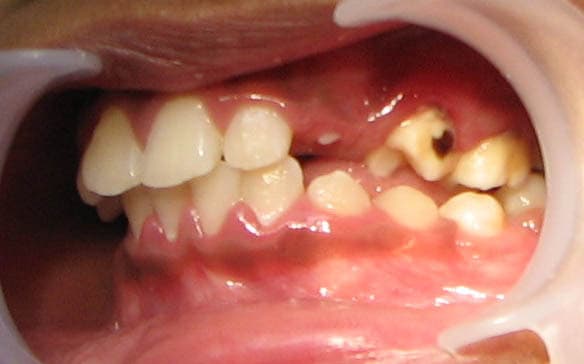

Avez-vous une idée de la lésion amélaire observée sur la 24 ?

La petite patiente a 8 ans et a été en malnutrition dans sa petite enfance (originaire des Philippines)

De multiples caries avec fistules ont été présentes et certaines encore en bouche.

Le tissu est noir et dur à la sonde. La dent a fait son éruption il y a quelques mois seulement. Donc l'hypothèse de la carie arrêtée ne tient pas. Il n'y a pas de perte de substance.